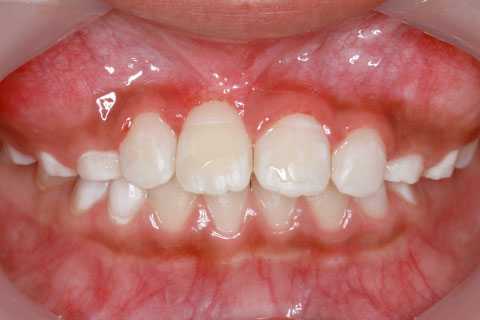

治療前

8歳女性

1年0ヶ月

なし

35万円

マルチブラケットを用いた矯正治療

歯肉切除により歯冠を露出させて引っ張り出す治療法

右上1番を露出させるため、歯肉切開が必要になるため、外科処置における疼痛や腫脹のリスクを説明した。また、右上1番を牽引しても理想的な位置にもっていけない場合もあると説明。